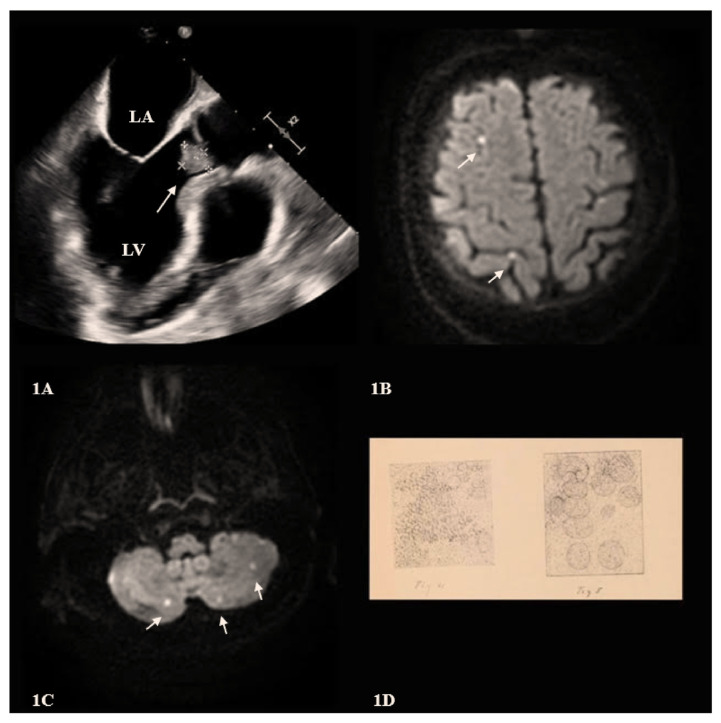

The patient in this case was a 72-year-old female who presented with altered mental status and was ultimately diagnosed with pneumococcal endocarditis. On physical examination, no abnormal cardiac murmurs were detected. This case highlights an important lesson: pneumococcal endocarditis, though rare, is a life-threatening condition with a high mortality rate and should be a top consideration in patients with S. pneumoniae bacteremia, even when the cardiac exam is relatively unremarkable.